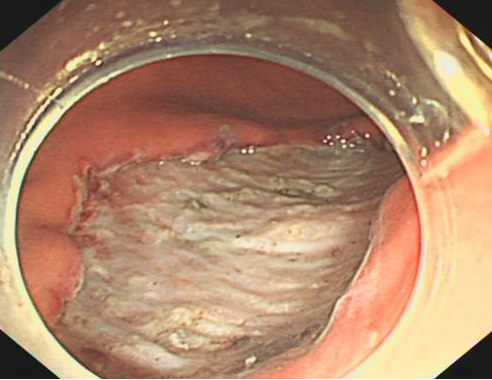

病灶切除

什么是260胃镜医视点 | 精细胃镜使内镜进入“显微时代”_https://www.jmylbn.com_新闻资讯_第9张

病变标本

患者基本情况符合内镜精查,于内镜科行精细胃镜检查。精细内镜报胃体下部大弯侧Ⅱc型病变,活检病理回报:考虑为黏膜层未分化型癌,且小于2厘米,表面无溃疡,符合内镜下治疗的适应证,2022年5月于内镜科行内镜黏膜下剥离术。该患者术后病理回报与之前精查胃镜结果基本一致,符合黏膜内浅表印戒细胞癌,该患者病灶小,白光下极易与正常胃黏膜混淆。此例早癌患者被及时发现,进行内镜下治疗,既属于治愈性切除,又拥有损伤小、费用低、术后恢复快的优势,通过内镜精查达到了早发现、早诊断、早治疗目的。